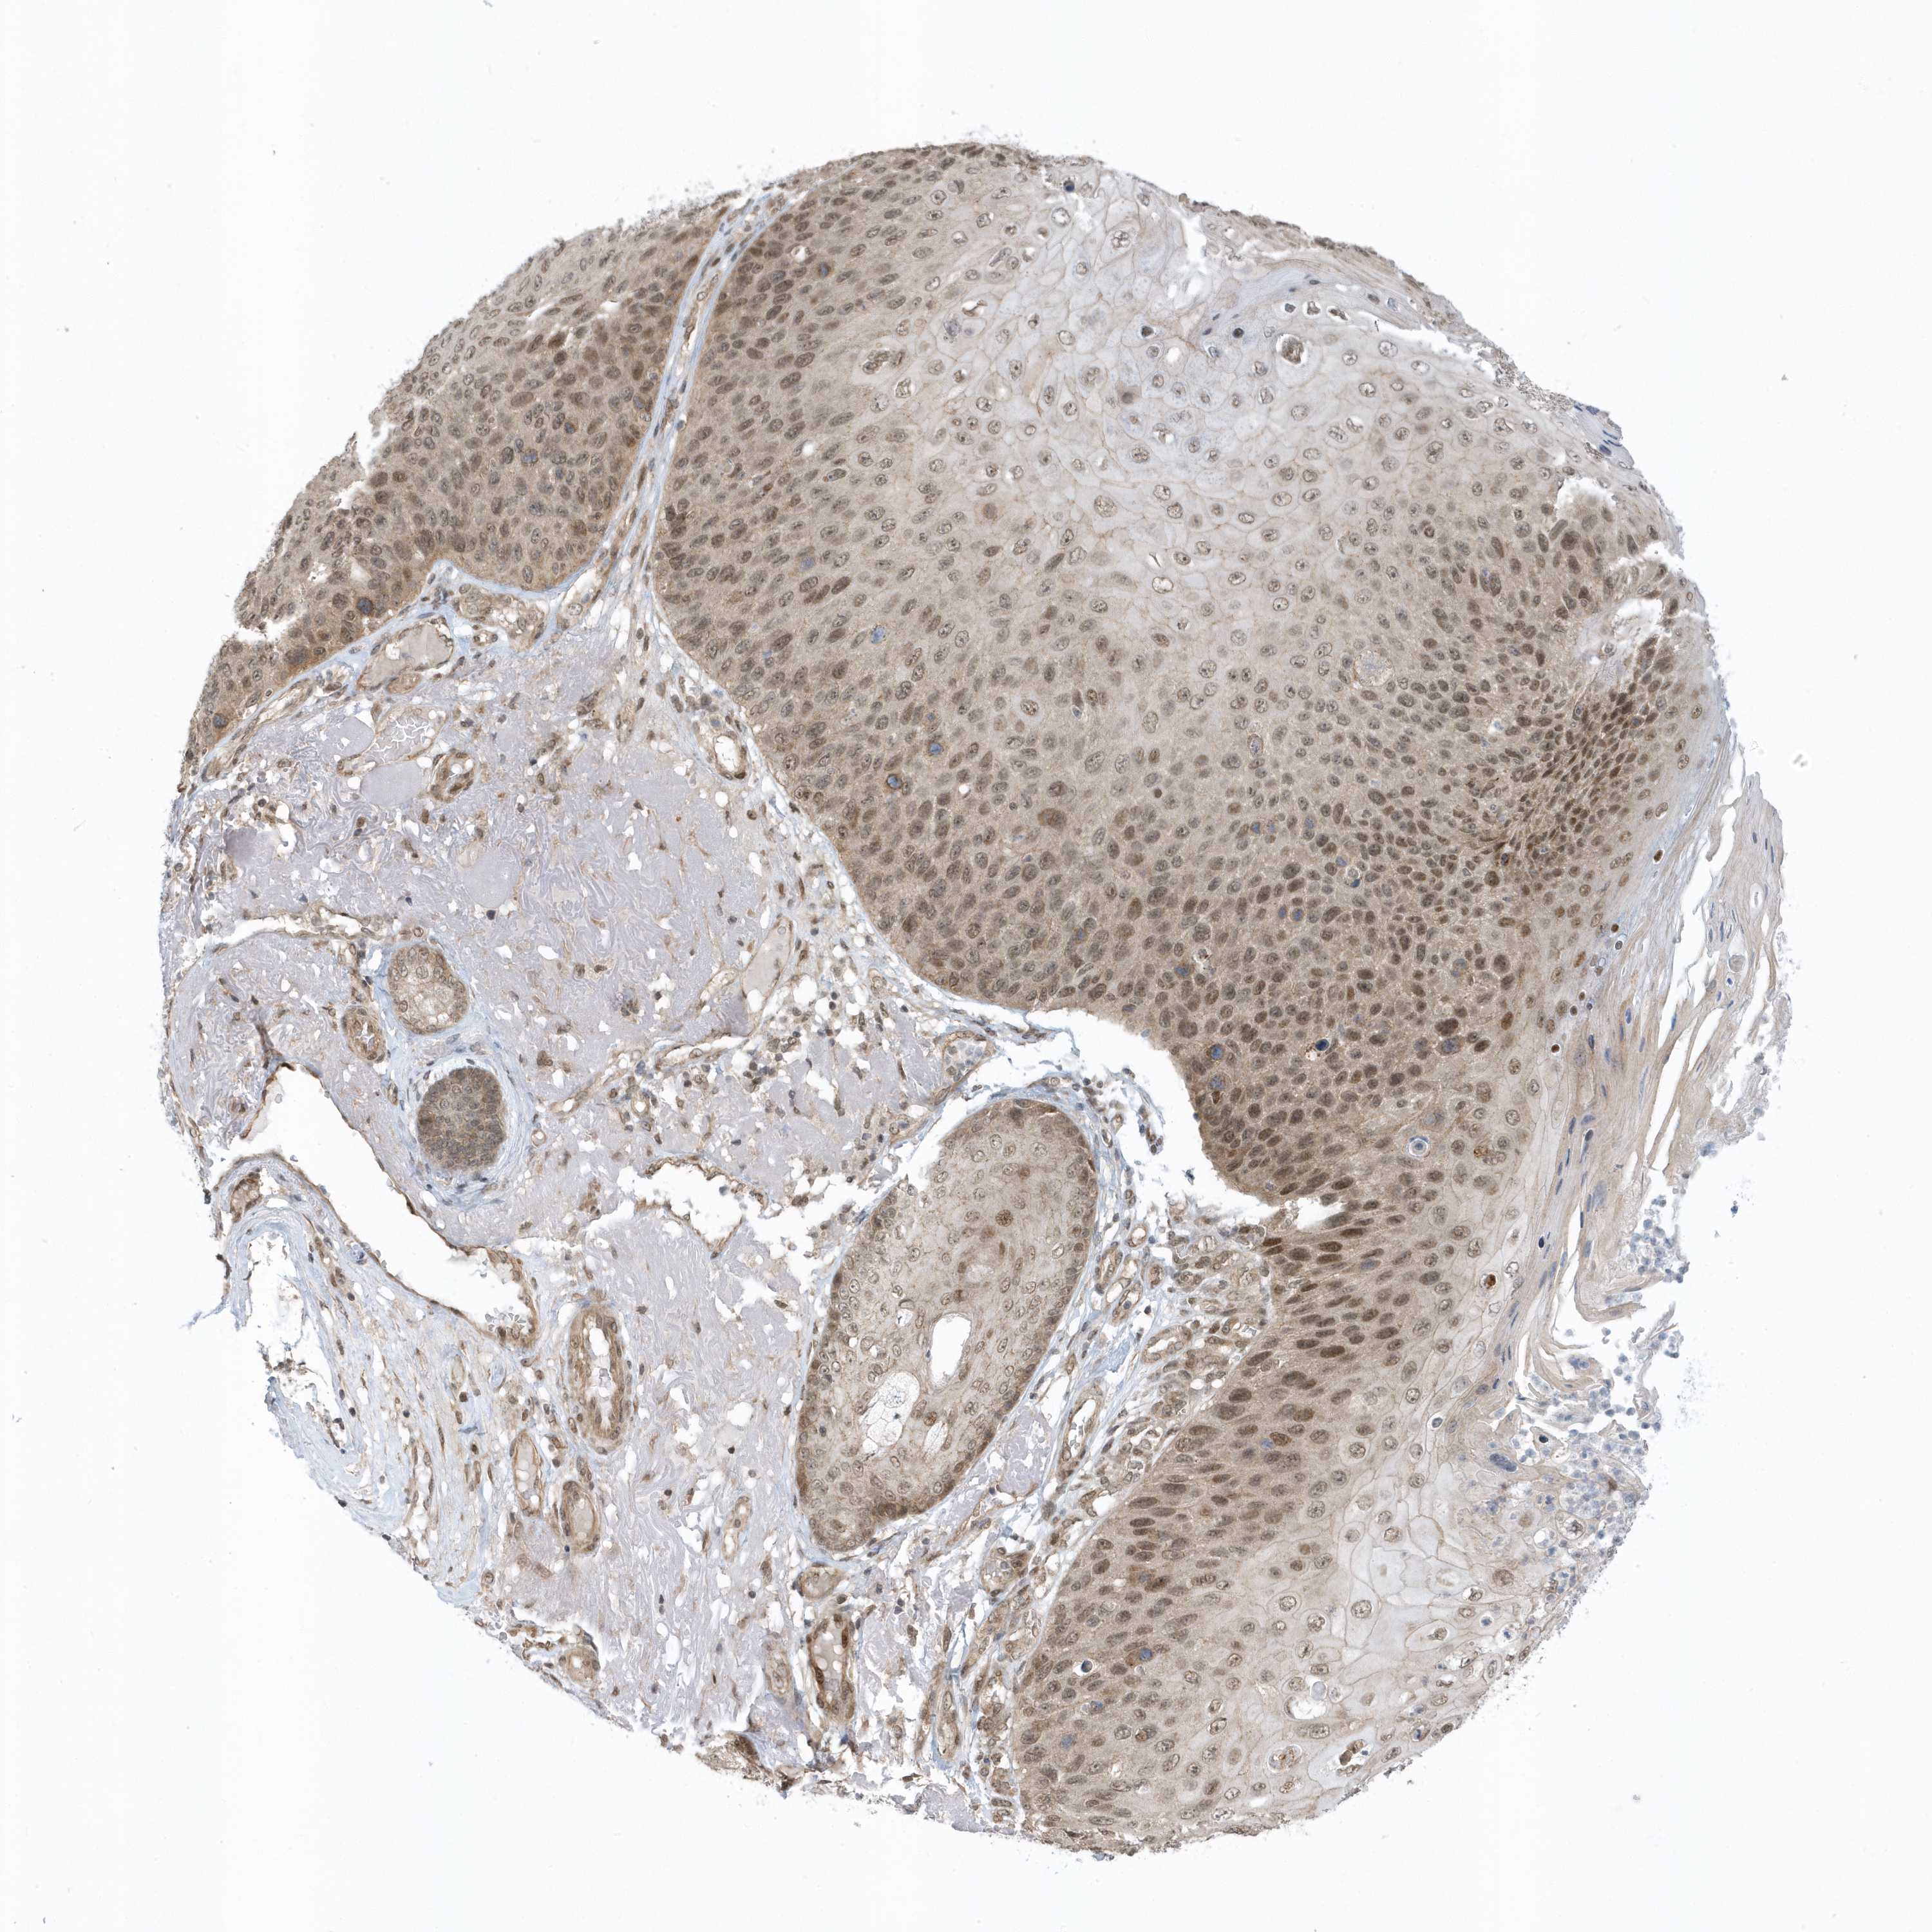

Basal cell and squamous cell cancer

SKIN CANCER - Protein expressioni

A mouse-over function shows sample information and annotation data. Click on an image to view it in a full screen mode. Samples can be filtered based on level of antibody staining by selecting one or several of the following categories: high, medium, low and not detected. The assay and annotation is described here.

Each image is clickable and will lead to virtual microscopy that enables deeper exploration of all samples and also displays staining intensity scores, fraction scores and subcellular localization as well as patient and tissue information for each sample.

Antibody HPA035844

Antibody HPA035845

Basal cell carcinoma